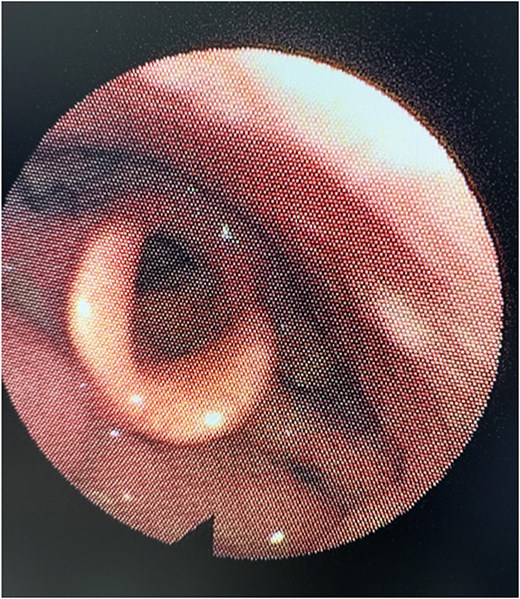

The patient was followed up for 6-months, and repeated flexible nasal endoscopy showed a well-healed mucosa with no recurrent lesions or asymmetry in the aryepiglottic fold (Fig. 4). The patient reported complete resolution of dysphagia and dyspnea symptoms.

Six-month post-operative nasal endoscopy. The left aryepiglottic fold demonstrates well-healed mucosa with no residual mass, scarring, or asymmetry. The laryngeal structures appear normal with no evidence of recurrence.